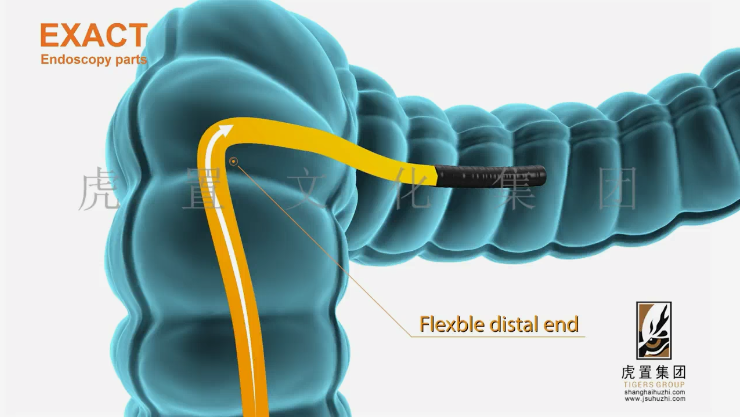

特效是提升三维动画工业机械设备表现力的重要手段。在合成阶段,可添加粒子特效模拟设备运行时的火花、烟雾,或使用光效增强金属表面的高光质感。例如,在展示激光切割设备的动画中,通过粒子特效制作激光束切割材料时产生的飞溅火花,配合光线追踪特效,呈现激光的高亮与穿透效果,让画面更具真实感和震撼力。